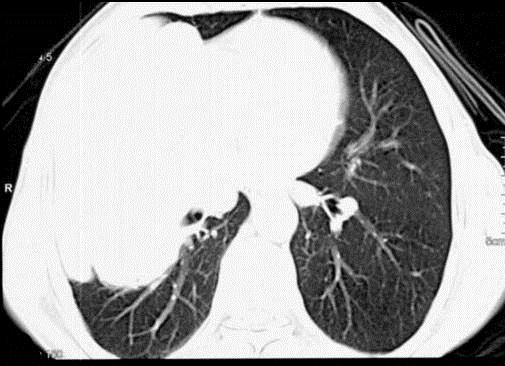

问题 50岁,男性,右侧胸痛、咳嗽、咯血3个月,请结合图像选择最可能的诊断 ( )

选项 A.纵隔肿瘤 B.肺结核 C.肺癌 D.胸膜间皮瘤 E.韦格肉芽肿

答案 C